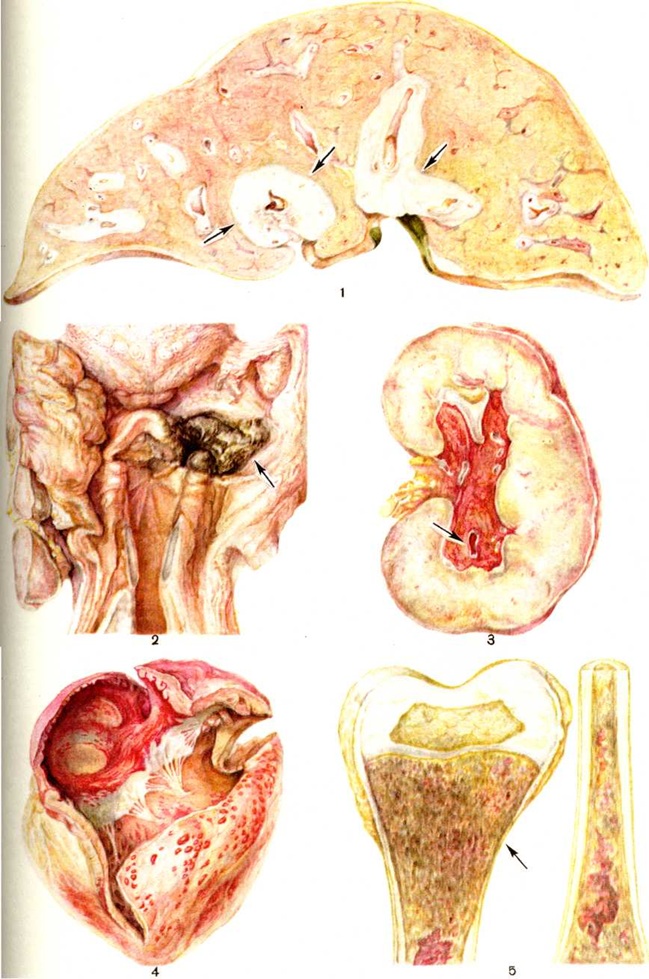

В ряде случаев выявляется увеличение селезёнки, лимфатических узлов, печени, которое, однако, выражено не столь значительно, как при хронический Лейкозы Вес селезёнки в большинстве случаев увеличивается в 2— 3 раза по сравнению с возрастной нормой, реже размеры и вес селезёнки остаются нормальными даже при наличии лейкозной инфильтрации, изредка возможно её значительное увеличение (до 700—1000 грамм). Зависимости между степенью спленомегалии (смотри полный свод знаний) и длительностью заболевания (по клинические, данным), а также формой острого Лейкозы не установлено. Ткань селезёнки на разрезе красного цвета, со стёртым рисунком строения, иногда имеются инфаркты, пульпа даёт обильный соскоб. Разрывы капсулы даже при массивной лейкозной инфильтрации возникают редко. Увеличение лимфатических, узлов может быть выражено в различной степени и обычно является системным, иногда увеличены лимфатических, узлы одной анатомической области. В некоторых случаях лимфатических, узлы не увеличены. Поражённые лимфатических, узлы мягкой консистенции, не спаяны между собой, ткань их розово-красного цвета. Печень, как правило, увеличена незначительно, на разрезе иногда видны мелкие серовато-белые полоски, соответствующие зонам лейкозной инфильтрации. Специфические разрастания часто выявляются в желудочно-кишечном тракте. В таких случаях наблюдается набухание дёсен, увеличение миндалин, групповых фолликулов (пейеровых бляшек) тонкой кишки и солитарных фолликулов толстой кишки, участки диффузного утолщения стенки желудка и кишечника. Характерны обширные очаги некроза слизистой оболочки желудочно-кишечные тракта с изъязвлением. Изредка наблюдается перфорация стенки кишки, перитонит. При значительной распространённости процесса узелковые или диффузные беловатые разрастания лейкозной ткани выявляются в коже, эпикарде, плевре, почках, сердце, половых органах, а у детей — в вил очковой железе. На фоне системной лейкозной инфильтрации у детей примерно в 50% случаев и у взрослых в 10% случаев острых Лейкозы, нелеченых или устойчивых к терапии, наблюдаются обширные узловатые разрастания различной локализации (цветной рисунок 1—8).

При острых Лейкозы часто выявляется поражение центральная нервная система— нейролейкоз — в виде инфильтрации мозговых оболочек и вещества головного и спинного мозга, черепных нервов. Такое поражение имеет место при различных формах острого Лейкозы чаще всего при остром лимфобластном Лейкозы у детей. Лейкозная инфильтрация мозговых оболочек может быть изолированной или сочетается с патологический изменениями вещества головного мозга. Макроскопически выявляется очаговое или диффузное утолщение паутинной оболочки, обширные кровоизлияния в ней, реже поражается твёрдая мозговая оболочка. При лейкозной инфильтрации головного мозга обнаруживаются множественные темно-красные очаги — от точечных до нескольких сантиметров в диаметре, преимущественно в белом веществе. Иногда возникают обширные участки красного размягчения вещества мозга с прорывом в желудочки мозга и под твёрдую мозговую оболочку.

В костном мозге, по данным трепанобиопсии, на первых стадиях заболевания скопления бластных клеток являются очаговыми, в достаточном количестве обнаруживаются элементы деятельного костного мозга. Нередко наблюдаются острые расстройства кровообращения, участки гипоплазии, могут обнаруживаться некрозы. Прогрессирование заболевания характеризуется увеличением числа и размеров лейкозных разрастаний, их слиянием, а затем диффузной инфильтрацией ткани костного мозга. Количество нормальных кроветворных клеток заметно уменьшается. Часто имеется инфильтрация надкостницы, возможно распространение процесса в окружающие мягкие ткани. Развитие лейкозных разрастаний сопровождается выраженным рассасыванием костной ткани, преимущественно по типу гладкой резорбции. Очень редко в этом процессе принимают участие остеокласты. Вследствие частичного, а местами и полного рассасывания костных балок происходит значительное расширение костномозговых полостей, истончение, а в некоторых участках разрушение кортикального слоя. В раннем детском возрасте резкие изменения наблюдаются в зоне энхондрального окостенения. При острых Лейкозы редко отмечается очаговое новообразование атипичной костной ткани, богатой остеоидом, разрастание фиброзной ткани. Наряду с мелкими фокусами некроза иногда возникают обширные инфарктообразные коагуляционные некрозы, определяемые макроскопически в виде жёлто-белых сухих участков; в окружности наблюдаются кровоизлияния, возможно скопление макрофагов (рисунок 1). В области лейкозных разрастаний нередко обнаруживается истончение и частичный распад ретикулярных волокон. Описаны наблюдения с очаговым или диффузным миелофиброзом, который чаще выявляется при миелобластном Лейкозы. В таких случаях при пункции обычно не удаётся получить костный мозг и для установления диагноза необходимо исследование материала трепанобиопсии.

Лейкозная инфильтрация ткани селезёнки и лимфатических, узлов сопровождается уменьшением размеров (рисунок 2) и числа фолликулов вплоть до полного их исчезновения. В селезёнке часто наблюдается инфильтрация трабекул с разволокнением стенок трабекулярных сосудов, с деформацией и сужением их просвета, имеются поля кровоизлияний. В лимфатических, узлах вначале возникают очаговые инфильтраты, которые по мере прогрессирования болезни увеличиваются в размерах, и поражение становится диффузным.

Острый лимфобластный лейкоз, особенно у детей, чаще всего характеризуется массивным поражением всех групп лимфатических, узлов, селезёнки, вилочковой железы, нередко со значительным их увеличением. В вилочковой железе лейкозная инфильтрация располагается внутри долек и обусловливает разрушение эпителиального ретикулума. В лёгких разрастания локализуются преимущественно в стенках и окружности бронхов, в печени — в области портальных полей. При распространённом процессе пролифераты выявляются в желудочно-кишечные тракте, центральная нервная система, почках, половых органах и другие В детском и юношеском возрасте обширные узловатые разрастания чаще возникают при данной форме и локализуются главным образом в вилочковой железе и лимфатических, узлах переднего средостения. Нередко они распространяются на перикард, плевру, ткань лёгких, что приводит к образованию массивного опухолевого конгломерата. Разрастания в костном мозге и других органах состоят из бластных клеток лимфоидного происхождения, которым свойственно высокое ядерно-цитоплазматическое соотношение.

Острый миелобластный лейкоз в развёрнутой стадии болезни характеризуется выраженной лейкозной инфильтрацией костного мозга и других органов. В печени лейкозные разрастания локализуются в синусоидных капиллярах и в области портальных трактов. Аналогичное расположение инфильтратов имеется и при других более редких формах острого Лейкозы (монобластном, миеломонобластном, недифференцируемом, промиелоцитарном и другие), поэтому данный признак не может служить основанием для разграничения форм острого Лейкозы В лёгких лейкозная инфильтрация обычно выявляется по ходу межальвеолярных перегородок с выходом бластных клеток в просветы альвеол (рисунок 3), возможна локализация и в окружности бронхов, сосудов, междольковых перегородках. У детей при этой форме Лейкозы лейкозные разрастания в вилочковой железе располагаются в соединительнотканных прослойках, сдавливают дольки, что сопровождается увеличением количества аргирофильных волокон. У взрослых типично развитие множественных узлов в надкостнице плоских и трубчатых костей, почках, печени, половых железах, жировой клетчатке (подкожной, ретробульбарной, клетчатке большого сальника и малого таза), иногда в коже, конъюнктиве, твёрдой мозговой оболочке и костном мозге. В ряде случаев в области опухолевых узлов и системных поражений имеется зелёное окрашивание ткани (хлоролейкоз). Аналогичные изменения могут выявляться и при Лейкозы у детей.

При остром мегакариобластном лейкозе в костном мозге выявляется большое количество атипичных мегакариоцитов и мегакариобластов, которые диффузно рассеяны в ткани, а местами образуют скопления (рисунок 4). Такие же клетки в значительном количестве содержатся в ткани и синусах селезёнки, лимфатических, узлов, просветах мелких сосудов печени, лёгких и других органов.

При микроскопическом исследовании в костном мозге преобладают незрелые и зрелые клетки гранулоцитарного ряда (рисунок 5), соотношение которых может варьировать. По данным трепанобиопсий, в начальной стадии заболевания ещё в достаточном количестве сохраняются элементы эритропоэтического и мегакариоцитарного ряда. По мере прогрессирования процесса их число снижается, исчезают жировые клетки. Характерны глубокие изменения в строме в виде сочетания процессов деструкции с увеличением количества фибробластов, аргирофильных и иногда коллагеновых волокон. Изучение костного мозга методом трепанобиопсии в динамике свидетельствует о том, что миелофиброз постепенно нарастает и бывает более выражен у больных с повторными ремиссиями и обострениями заболевания. В отдельных случаях в костном мозге имеют место обширные очаги некроза; постоянно наблюдается выраженное рассасывание костной ткани. В селезёнке и лимфатических узлах в развёрнутой стадии болезни обнаруживается диффузная инфильтрация миелоидными элементами, атрофия лимфатической ткани. Лейкозное поражение селезёнки часто сопровождается выраженным в различной степени фиброзом красной пульпы, образованием полей склероза, что наряду с инфильтрацией и полнокровием является причиной увеличения её веса. Для хронический миелолейкоза характерна локализация лейкозных инфильтратов в печени по ходу синусоидных капилляров (рисунок 6), в лёгких — в области межальвеолярных перегородок. Нередко наблюдается инфильтрация стенок мелких бронхов, сосудов, плевры. Реже, чем при острых Лейкозы очаги лейкозной инфильтрации возникают в почках, мышце сердца, в стенках желудочно-кишечные тракта, в оболочках и веществе головного мозга, коже, железах внутренней секреции и других органах.

Микроскопически в костном мозге обнаруживается системное разрастание лимфоцитов. При обострении процесса наряду со зрелыми лимфоцитами выявляются пролимфоциты и лимфобласты. В костном мозге выделяют три типа инфильтрации: диффузную, диффузно-очаговую, очаговую. При первых двух типах инфильтрации расширенные полости костного мозга содержат значительное количество лимфоцитов, диффузно рассеянных в ткани или образующих наряду с этим компактные скопления (диффузно-очаговый тип). В отличие от других форм Лейкозы даже при массивной инфильтрации в костном мозге сохраняются небольшие очаги нормального кроветворения, не исчезают полностью жировые клетки. Для хронический лимфолейкоза характерно резкое рассасывание костной ткани и отсутствие признаков её новообразования. Данные прижизненного гистологический исследования костного мозга показывают, что очаговый тип инфильтрации наблюдается в ранние стадии заболевания. В отличие от лимфоидных узелков, выявляемых в норме в костном мозге, а также от реактивной нодулярной лимфоидной гиперплазии, сопутствующей ряду заболеваний, при хронический лимфолейкозе очаговые скопления лимфоцитов характеризуются довольно крупными размерами, лишены чётких границ, имеют тенденцию к слиянию, содержат наряду со зрелыми лимфоцитами пролимфоциты и лимфобласты. Разграничение этих изменений с метастазами в костный мозг лимфоцитарной лимфосаркомы ввиду сходности морфологический картины основывается на особенностях клинические, проявлений заболевания. При развёрнутой картине хронический лимфолейкоза в лимфатических, узлах обнаруживается диффузная инфильтрация ткани лимфоцитами с полным стиранием рисунка, которая может проникать через капсулу в окружающую жировую клетчатку. В селезёнке в некоторых случаях видны резко увеличенные в размерах фолликулы без центров размножения, сливающиеся друг с другом, однако чаще имеется полное стирание рисунка вследствие диффузной инфильтрации ткани лимфоцитами. Нередко встречаются поля склероза. В печени обширные скопления лимфатических, клеток располагаются главным образом в области портальных полей (рисунок 7), но могут встречаться и в синусоидных капиллярах. В зонах инфильтрации нередко имеет место разрастание аргирофильных и коллагеновых волокон. Часто наблюдается расширение желчных капилляров и застой желчи, дистрофия, частичный некробиоз и некроз гепатоцитов. В лёгких разрастания локализуются в стенках бронхов, что приводит к нарушению их дренажной функции и способствует развитию пневмоний. Могут наблюдаться участки массивной лейкозной инфильтрации ткани лёгкого. При микроскопии гнездные скопления лимфоцитов нередко обнаруживаются в строме почек, оболочках и мышце сердца, половых железах, жировой клетчатке и так далее. Очень редко встречается специфическая инфильтрация оболочек и вещества головного мозга. Частой находкой является скопление лимфоцитов в просветах сосудов различных органов, особенно при значительном лейкоцитозе. В отдельных случаях при обострении хронический лимфолейкоза возникают массивные опухолевые разрастания, исходящие главным образом из лимфатических, узлов. Опухолевые массы состоят из крупных недифференцированных клеток с уродливыми ядрами, нередко в них обнаруживаются участки некроза, кровоизлияния. Характерен резко выраженный инфильтрирующий рост.